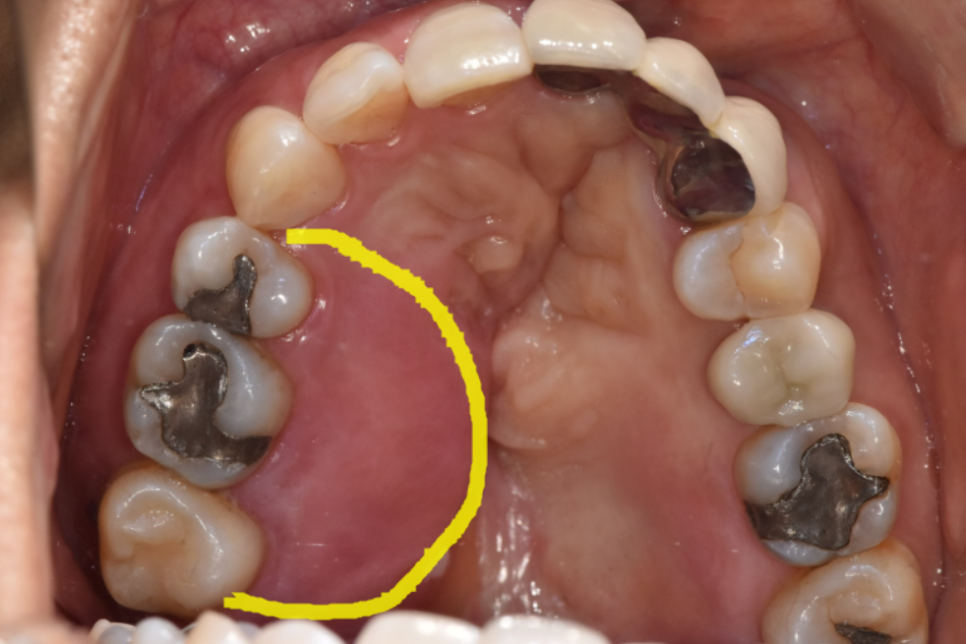

250121

게다가 입천장의 절반 이상이 심하게 부어올랐고,

잇몸에서는 고름이 나오고 있었습니다.

250121 치아 뿌리 염증 빼야 된다는 치아, 이렇게 살렸습니다. 치료 방법

이런 상태에서는 흔들림이 매우 심하기 때문에

대부분의 치과에서 발치를 권유하게 됩니다.